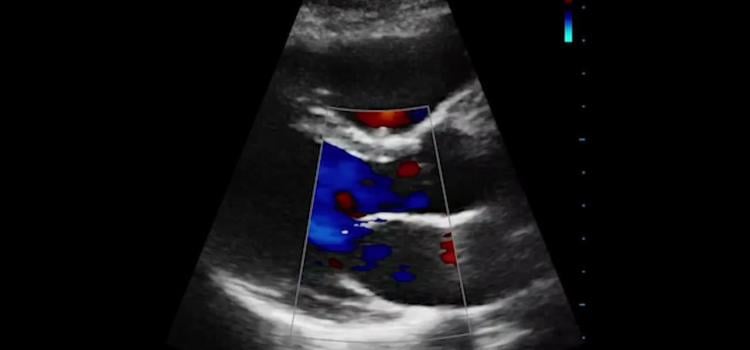

Here are two quick clinical examples of point-of-care ultrasound (POCUS) lung imaging and cardiac imaging using a GE ...

Recent advances in ultrasound image systems seen over the past year include the integration of artificial intelligence ...